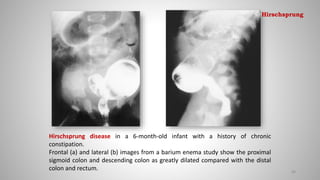

Hirschsprung disease in a 6-month-old infant with a history of chronic

constipation.

Frontal (a) and lateral (b) images from a barium enema study show the proximal

sigmoid colon and descending colon as greatly dilated compared with the distal

colon and rectum. 88